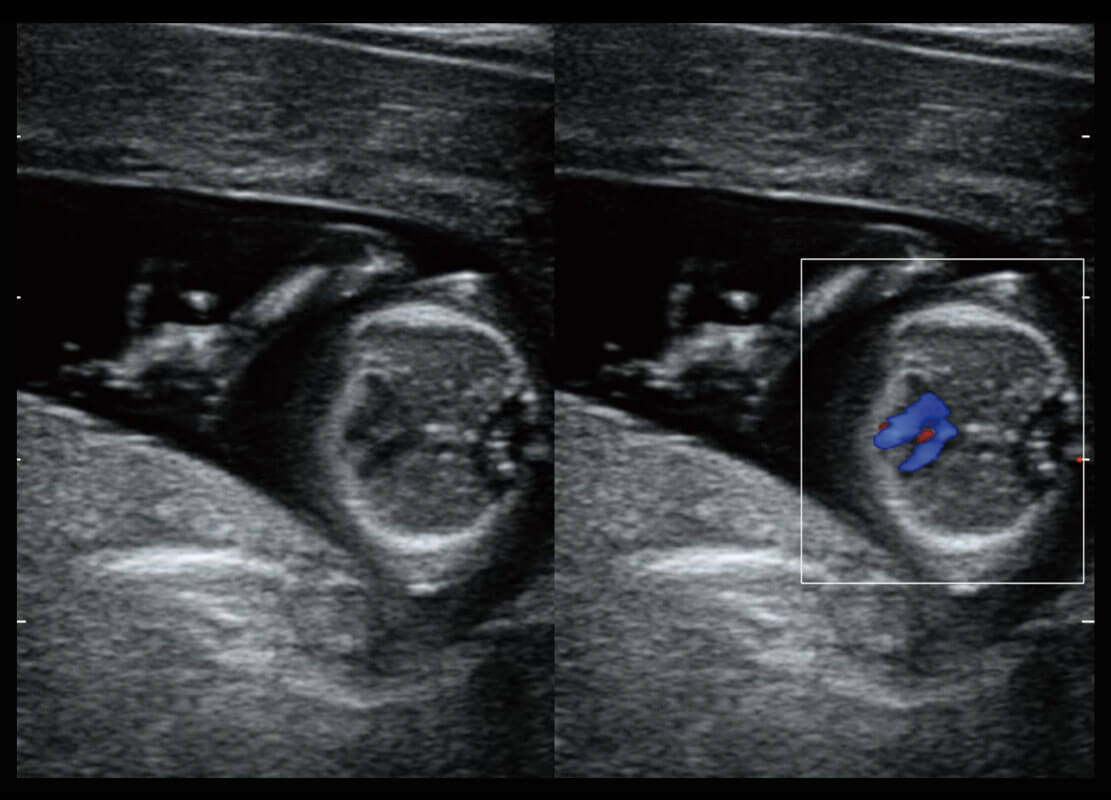

早孕-胎心

高分辨率容积成像-早孕胎儿

光影成像-孕囊

P60在胎儿早孕期超声筛查中为您带来优异的图像质量。